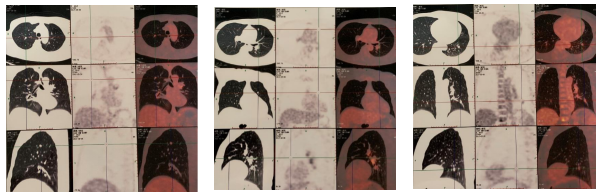

2017.3.31:患者因咳嗽两月入院复查,PET-CT示(如图1):T11椎体,L1椎体糖代增高影,伴混合性骨质破坏影,考虑骨多发转移;右上肺前段、右肺中叶、右肺下叶后基底段近胸膜处、左上肺前段、左下肺背段结节影,部分伴糖代谢轻度增高,多考虑多发转移瘤。

图1 PET-CT提示骨多发转移,肺部多发结节考虑转移瘤

肺部结节小,穿刺风险大,患者亦拒绝行肺部穿刺活检。2017年3月开始予以氟维司群 500mg治疗,同时予以唑来磷酸治疗,并且补充钙剂和维生素D3 。2017年9月复查PET-CT(如图2),疗效评价PR。后续继续予以氟维司群和唑来膦酸的治疗。

图2 T11椎体,L1椎体可见糖代谢增高的混合型骨质破坏影,现未见糖代谢增高,考虑治疗后肿瘤细胞处于抑制状态;原右肺中结节较前缩小,糖代谢未见明显增高,考虑治疗后肿瘤细胞处于抑制状态;原右肺上前段、右肺下叶后基底段近胸膜处,左上肺段、左下肺背段多发结节消失,考虑治疗后好转。